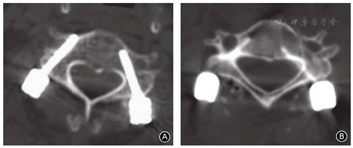

椎弓根螺钉位置:0级486枚、Ⅰ级8枚、Ⅱ级3枚、Ⅲ级0枚(表1,图3,图4,图5);寰椎置钉准确率为98.6%,枢椎准确率为97.7%,下颈椎准确率为97.6%。11枚螺钉穿破椎弓根皮质(Ⅰ级+Ⅱ级,表2),其中3枚螺钉为误置,但均为Ⅱ级(突破皮质<1.75 mm),穿破椎弓根内侧壁2枚(分别为C1和C4),穿破外侧壁1枚(C2),无穿破椎弓根上壁及下壁者。置钉的准确率为97.79%(0级),螺钉的偏出率为2.22%(Ⅰ级+Ⅱ级+Ⅲ级),椎弓根螺钉总误置率为0.60%(Ⅱ级+Ⅲ级)。

我们提出了C3~C7"峡部"的概念,即取经过"峡部"中外1/3的垂线与横突根部中点的水平线相交,交点为螺钉的进钉点;定义椎弓根中轴线在水平面上与峡部后外侧面形成的夹角为横向角;椎弓根中轴线在矢状面上与峡部后侧面形成的夹角为纵向角。在C3~C5取横向角分别为95.10°±3.96°、86.60°±3.35°、84.60°±4.95°;纵向角分别为71.25°±4.54°、69.90°±5.06°、76.15°±5.11°(图1)。在C6、C7置钉中,根据椎体峡部后侧面与峡部后外侧面有时会出现成角分为两类,当两者为同一平面时取横向角为59.71°±1.10°,选取纵向角为75.86°±1.12°;当两者有成角时取横向角89.61°±1.24°,选取纵向角为75.86°±1.12°(图2)。